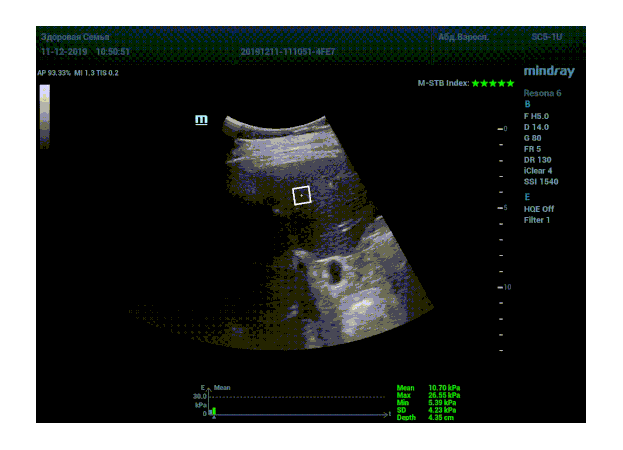

Определение плотности печени. Не ошибся ли оператор при измерении эластических свойств печени? Для оценки критериев качества предусмотрен индекс MBT, который покажет насколько «твердой» была рука оператора и двигалась ли печень. При MBT 5* рука тверда и показатели достоверны. Для оценки качества результатов используется IQR индекс, отображающий колебания показателей в точке измерения при расчете медианы. Показатели при IQR <30% считаются приемлемыми. Техника сканирования через межреберные промежутки требует размещение окна интереса на несколько сантиметром ниже капсулы, для исключения эффекта реверберации. Установка ROI на паренхиму без захвата сосудов, для исключения погрешностей измерения.

Стадия фиброза определяется по системе METAVIR Staging, построенной на данных биопсии и сопоставлении с данными эластографии. Своевременная диагностика фиброза, и начало его лечения, залог благоприятного исхода заболевания.